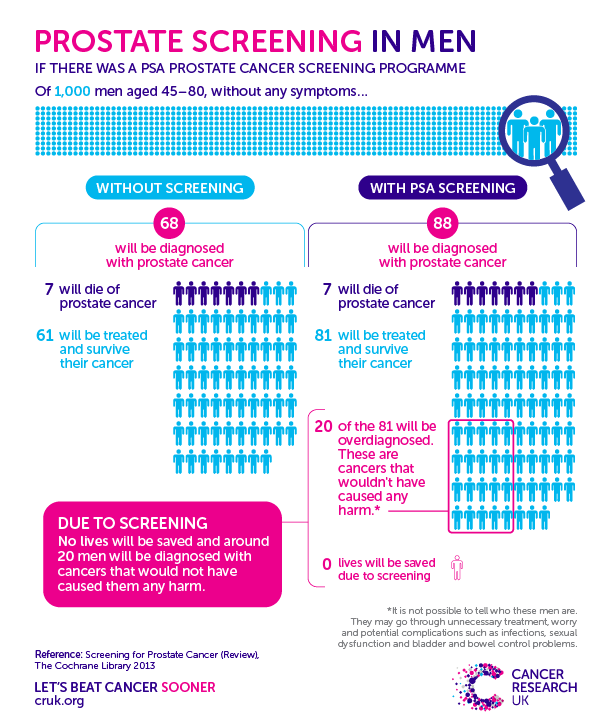

Prostate Cancer Screening Infographic – #BHtheChange

The Problem with PSA Screenings, Prostate Cancer and Risk

Prostate Cancer – Screening Saves Lives

Should You Be Screened for Prostate Cancer?

Cancer Research UK – Science blog